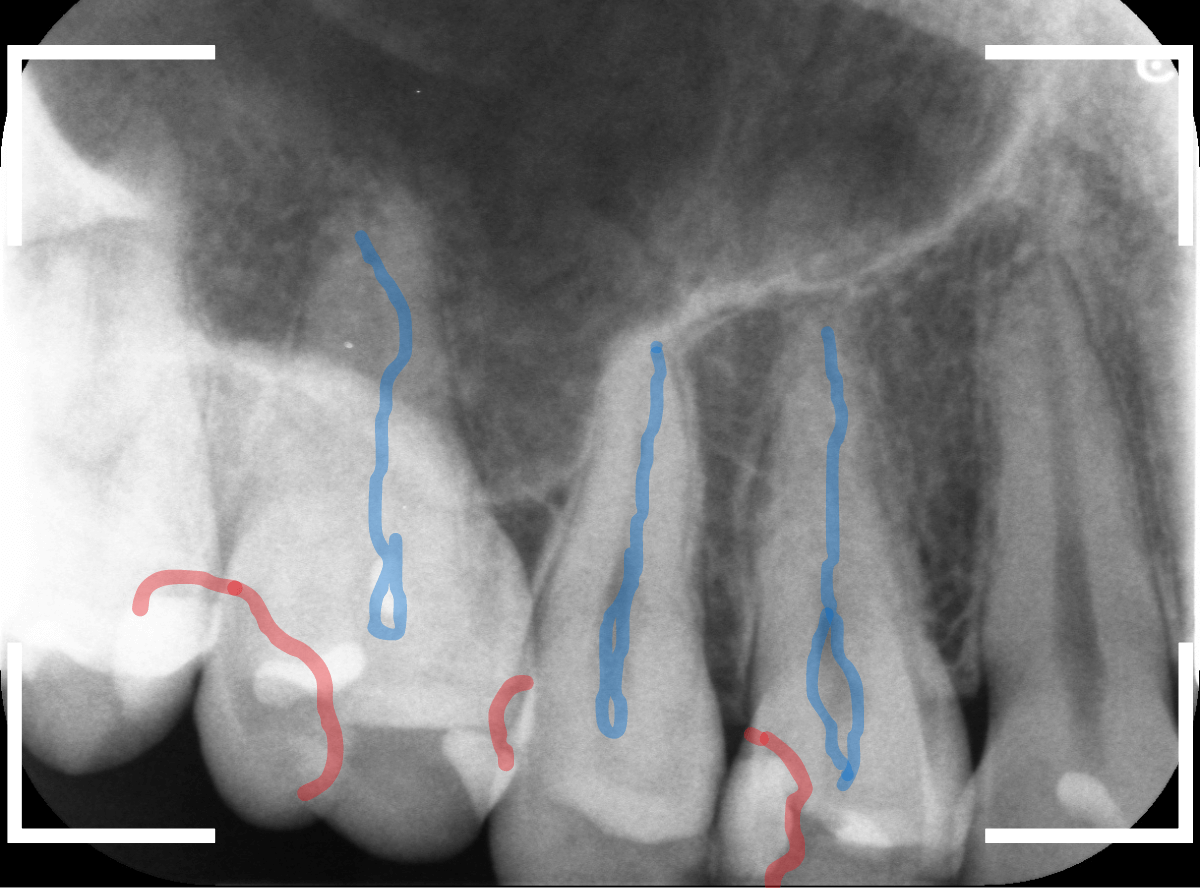

赤いラインが虫歯と思われる部分、青いラインが歯の神経です。

先ほどの〇部分は明らかな虫歯になっているのがわかります。

この辺りはレジンがつめてありますが、その下もうっすらと虫歯になっていそうです。

青い線が神経、赤い線が虫歯の範囲です。

奥歯の方がより深い虫歯に見えますが、再度打診で確認したところ、やはり手前の奥歯が痛むそうです。

赤い線が虫歯、青い線が歯の神経です。

歯のすきまから両側に虫歯が大きく広がっているのが確認できます。

青い線が歯の神経、赤い線が虫歯と思われる部分です。

2本とも、神経に達してしまいそうな大きな虫歯であると思われます。

青い部分が歯の神経、赤い部分が虫歯です。

レントゲン写真では、手前の歯との間も大きな虫歯になっているのがわかります。

そして、前後ともに神経まで達してしまっている虫歯に見えます。

赤い線が虫歯、青い線が神経です。

奥歯も神経に到達しそうな、大きな虫歯になっているのがわかります。

赤い部分が痛みを感じる歯の神経、青い部分が虫歯です。

もう、神経に触れそうな深い虫歯ですね、神経の治療が必要になるかもしれません。1年前に治療していれば。。。